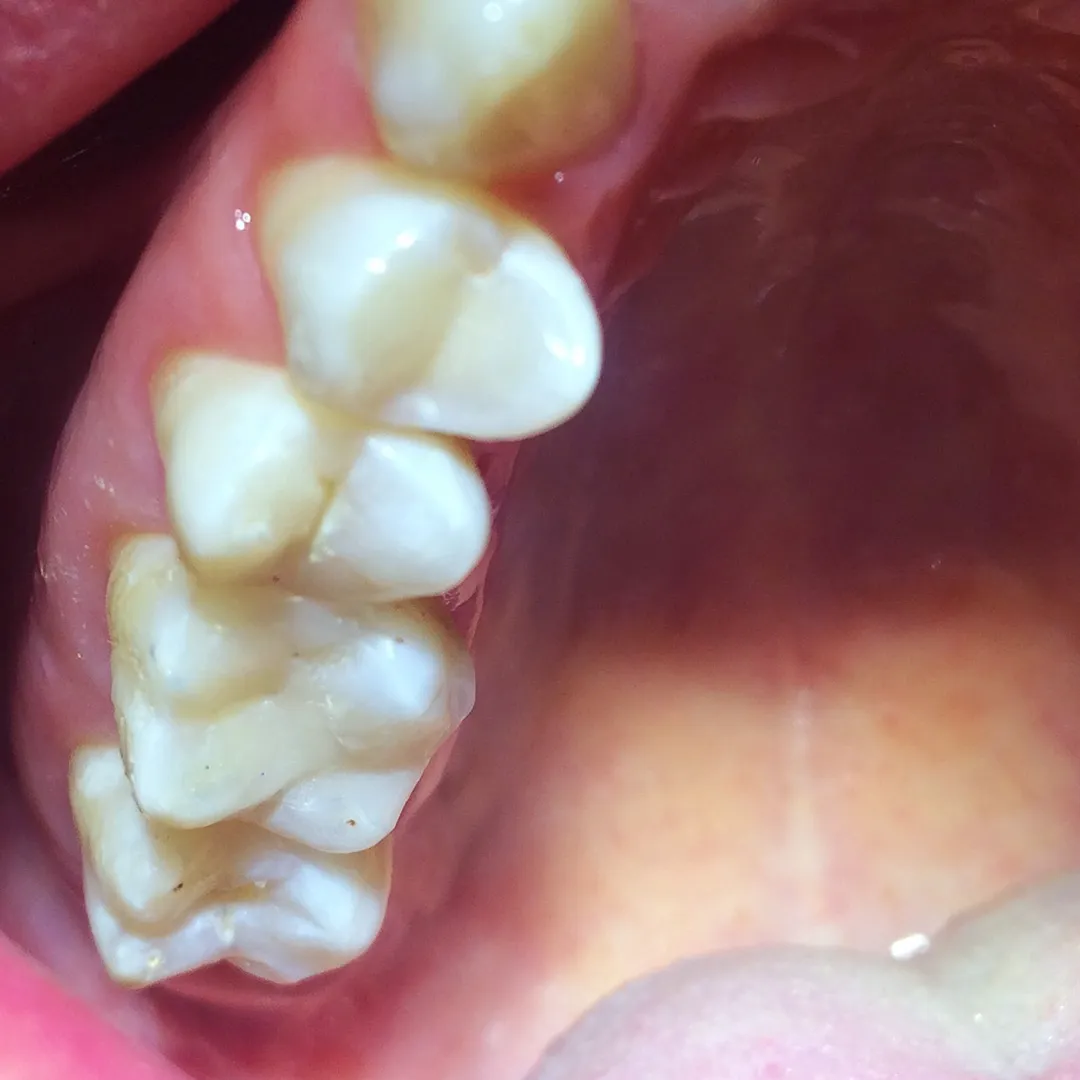

До и после лечения

Лечение кариеса зуба 4.6 композитом Filtek Posterior A3Смотреть работуСрок лечения:90 минутСумма лечения:6 000 руб.